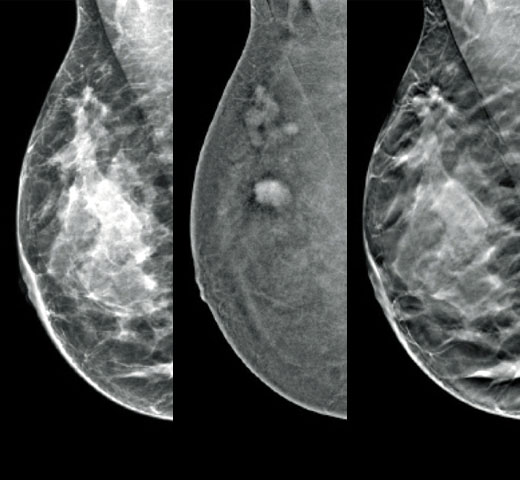

Architectural distortions, mass lesions, and bright spots commonly found in microcalcifications are more visible in the C-View 2D image than on the traditional FFDM 2D images or tomo slices.4,6-9

C-View 2D images are clinically proven3,5 and FDA approved to diagnostically replace the FFDM images within a tomosynthesis screening exam. The images are also a navigational aid to the tomosynthesis slice review. Published studies show that the low dose 3D Mammography exam finds invasive cancer earlier, while also reducing false positive recall rates compared to 2D alone.4,5,7

Architectural distortions, mass lesions, and bright spots commonly found in microcalcifications, are more visible in the C-View 2D image than on the traditional FFDM 2D image or tomo slice.4,6-9